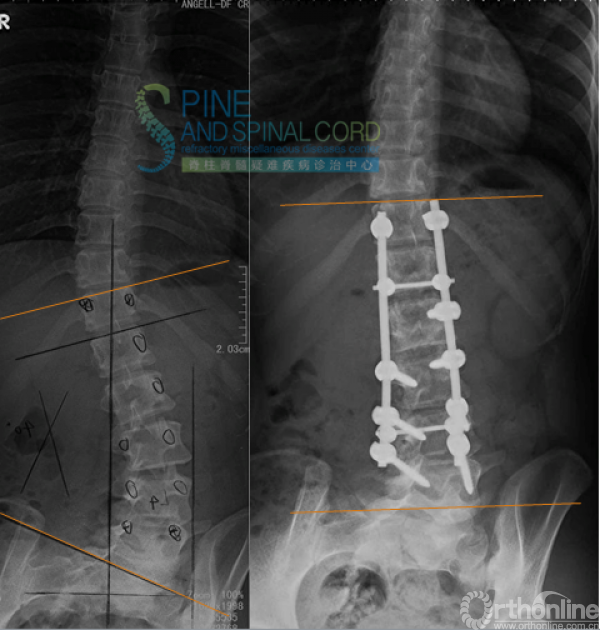

病例一 青少年型TCS

患者女,11岁,双下肢无力伴尿失禁11年

10年前曾行神经松解术

体检:双下肢肌萎缩,左侧马蹄内翻足、鞍区感觉障碍,双下肢反射亢进,babinski征阳性

Capsule术后半年复查

双下肢肌力明显增强;

可拄单拐行走;

排尿可控制,腹压增高时存在漏尿;

回归校园。